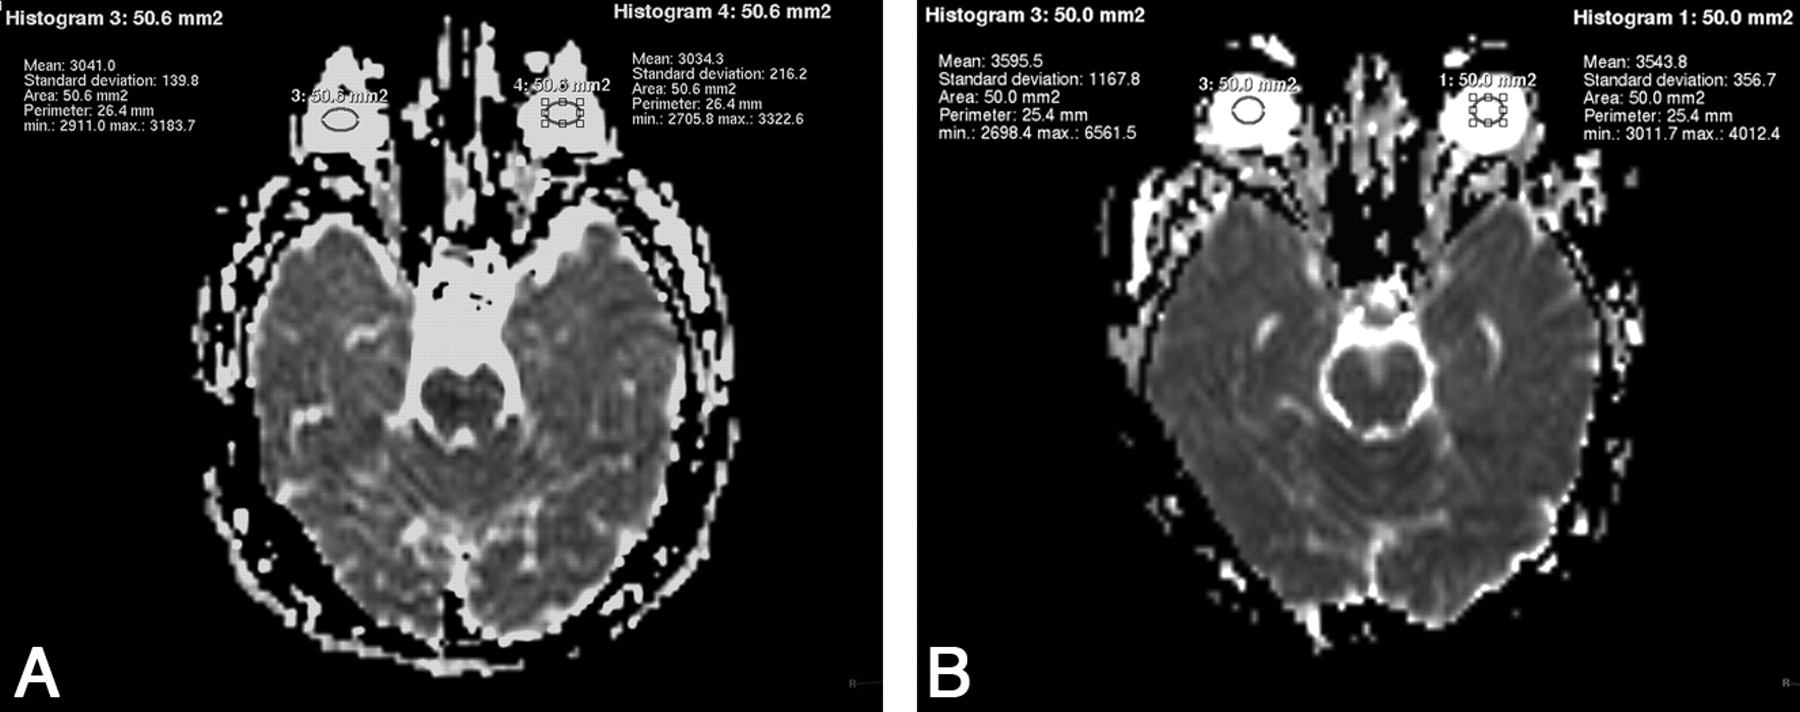

The Table presents the mean (plus the measure of variation) of the ADC values obtained for all study patients organized into decadic age groups. Post hoc analysis of the mean ADC values revealed that those of group 0 (0–10 years) were statistically different from the mean ADC values of all other age groups (P < .05) (Fig 1 A, -B). The mean ADC value observed in age group 1 (11–20 years) was found to be different from those of groups 3, 5, 6, and 7 as well (P < .05). While the mean ADC values of groups 2 and 4 were seen to be higher than that in group 1, this difference was not statistically significant.

A, ADC values obtained from the vitreous of a 4-year-old girl (W 1524/L 762). B, ADC values obtained from the vitreous of a 54-year-old man (W 1528, L 764).